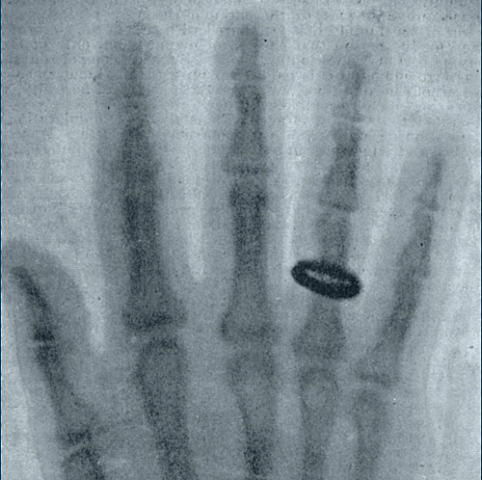

German physicist Wilhelm Roentgen discovers X-rays while experimenting with electricity in his laboratory. Soon after, he takes a radiograph of his wife’s left hand, as pictured. In 1902, Memorial Sloan Kettering pioneers the use of X-rays in cancer therapy by acquiring two X-ray machines.